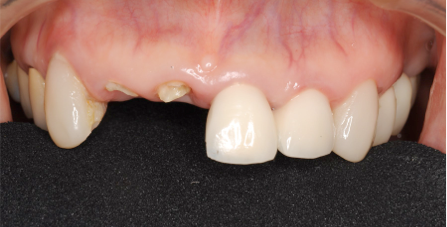

歯茎から歯が出ました

こうなるとそれに差し歯を被せれば

歯の長持ち度が全然違います